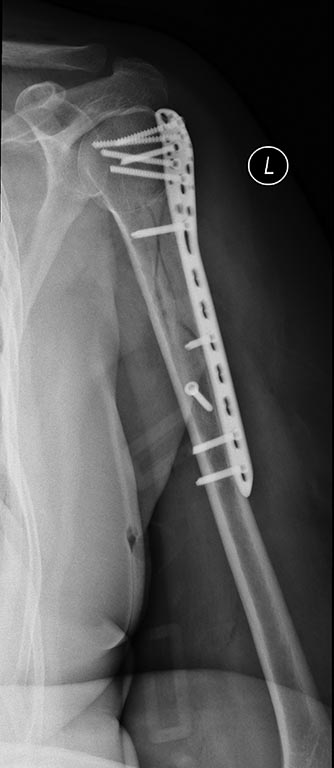

Re: Нестабильность остеосинтеза, несращение перелома плечевой кости.

Еще Рентгенограммы

то, что было после операции

Накостный остеосинтез получился приемлемым (по данным рентгенограмм), если были сомнения в стабильности, связанные с фрагментацией, то можно было бы перенести активизацию (разработку) на 1-2 недели.

пластина была явно коротка, можно было полечить по Сармиенто, сейчас гвоздь, вероятно, предпочтительнее